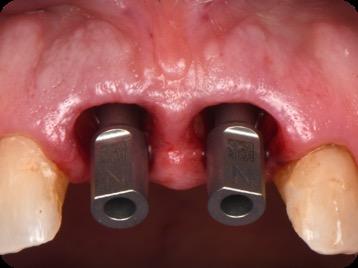

BioHorizons has introduced a new implant system that combines the advanced thread design of the Tapered Pro with the precision and stability of the Conelog conical connection. This integration delivers enhanced surgical handling, improved primary stability, and long-term biological benefits, supporting better patient outcomes in both aesthetic and functional zones.

This case was performed by Dr Homa Zadeh, DDS, PhD, a respected leader in periodontology and implant dentistry. Dr Zadeh’s approach emphasizes biologically driven protocols and evidence-based techniques, making this case a strong example of clinical excellence using the Tapered Pro Conical system. It involves the replacement of two front anterior teeth after they fractured off and the full restoration process.

Fig 7. Implants immediately after installation.

Fig 8. Scanbody installation for custom abutment and definite restoration fabrication.

Fig 9. Periapical radiograph for verification of proper seating of the scanbodies.